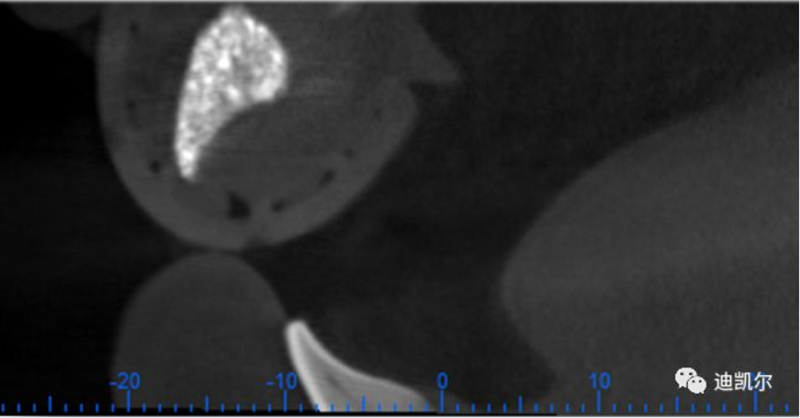

*CBCT顯示骨缺損嚴重,種植窩洞制備困難,種植體很難獲得初期穩(wěn)定性

患者佩戴此U型管開合拍攝CBCT,U型管中的放射標記點清晰顯影

設(shè)計軟件中,選擇適合的種植體

根據(jù)修復(fù)體形態(tài),軸向以及骨量將種植體放置最適合的位置